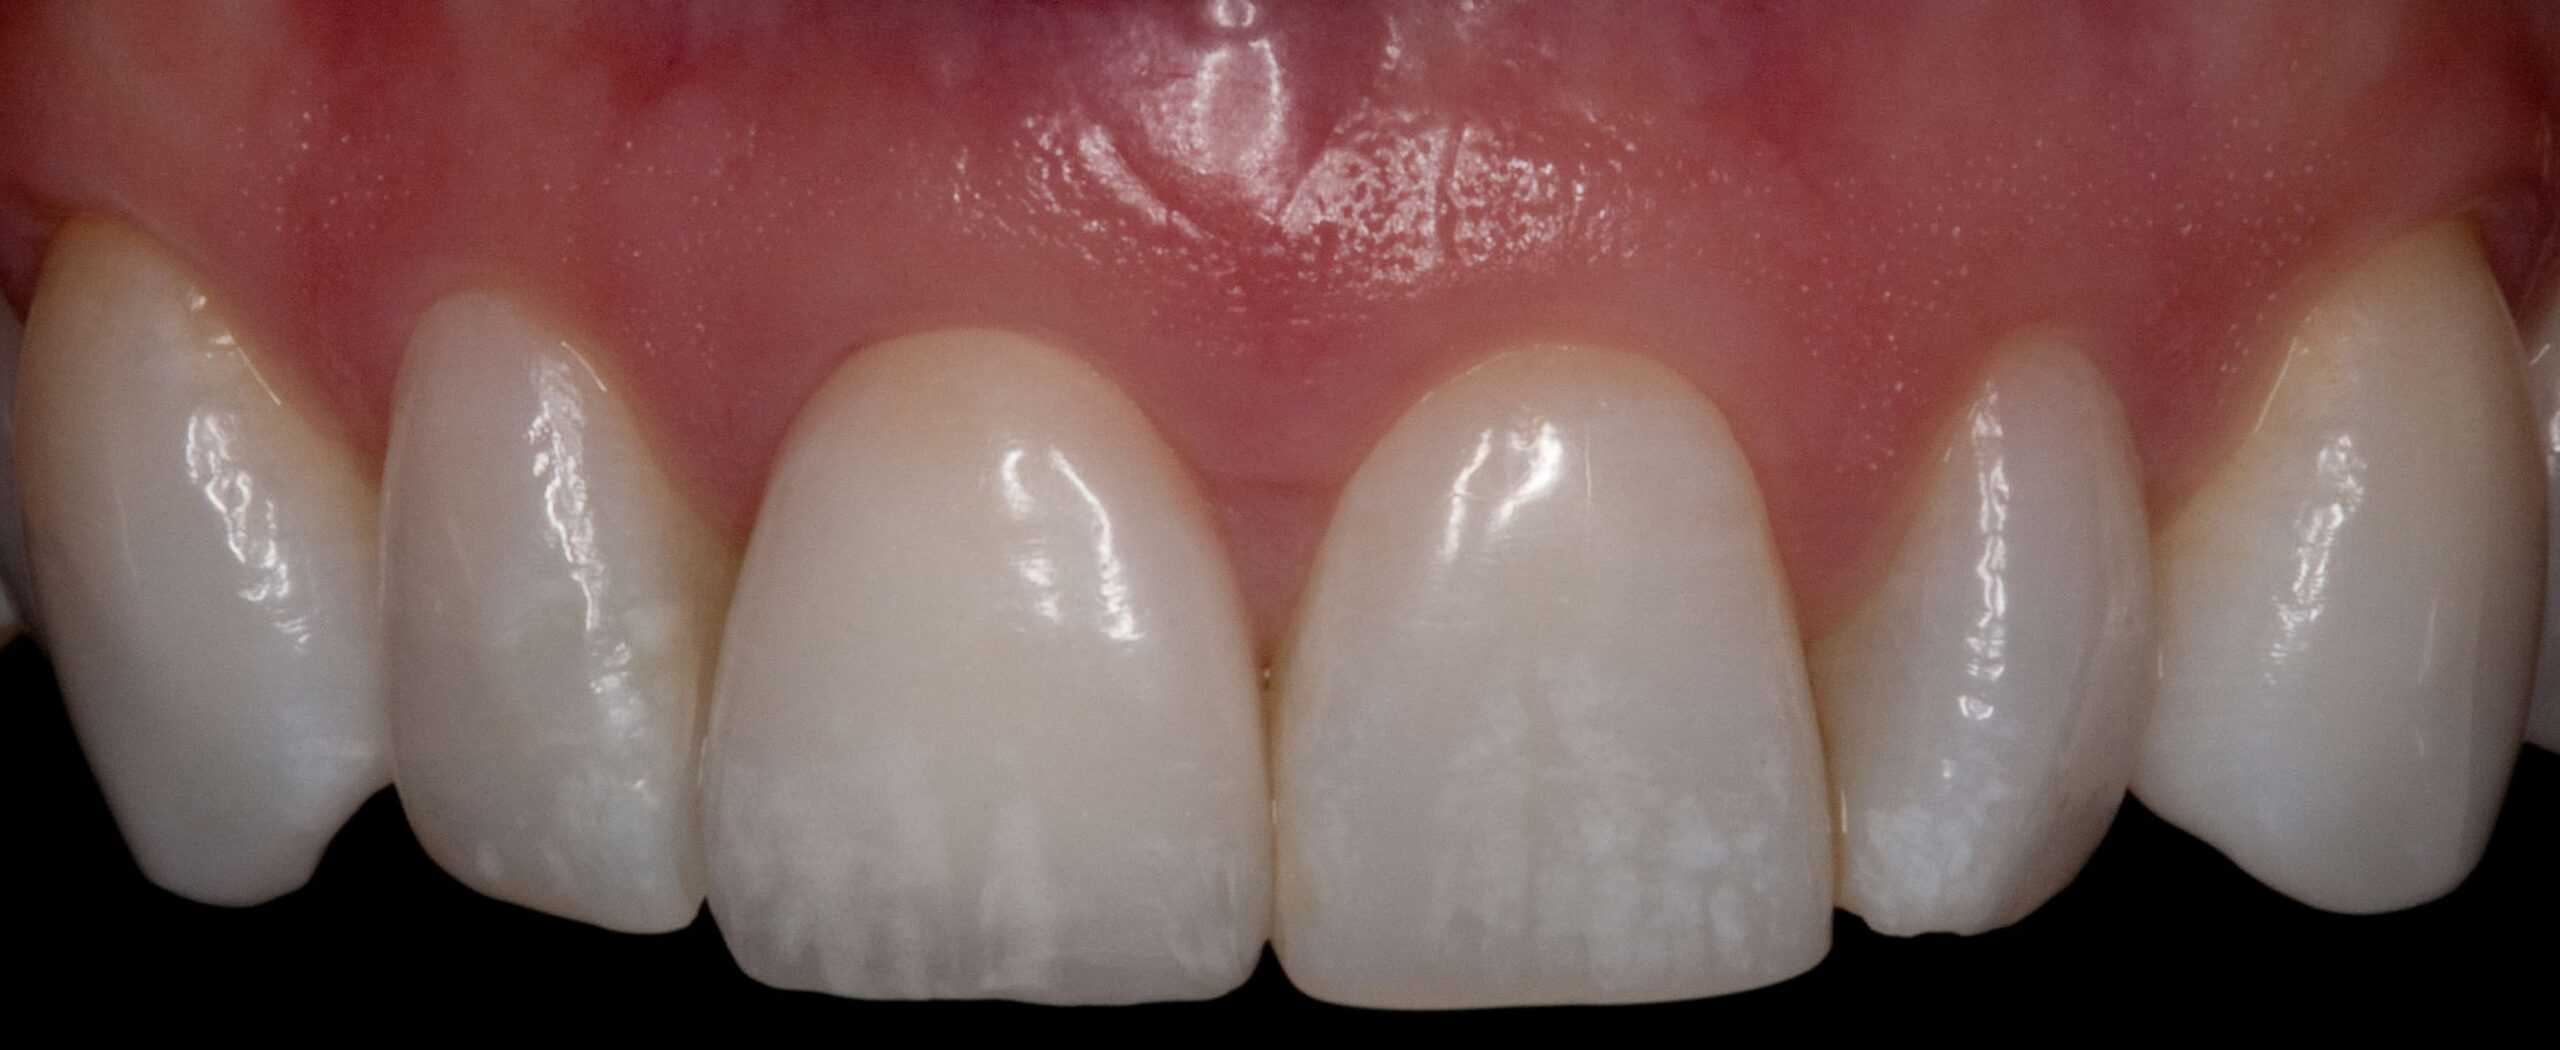

After: Single, all-ceramic crown attached to an all-ceramic, CAD-CAM designed and generated abutment (implant post). A delayed treatment approach was undertaken: tooth/root removal and grafting; 4 months healing; interim removable partial tooth replacement; implant placement; 6 months healing; proto-type (transitional fixed) implant crown, then the definitive implant restoration. The new tooth blends in perfectly with the natural, adjacent teeth.